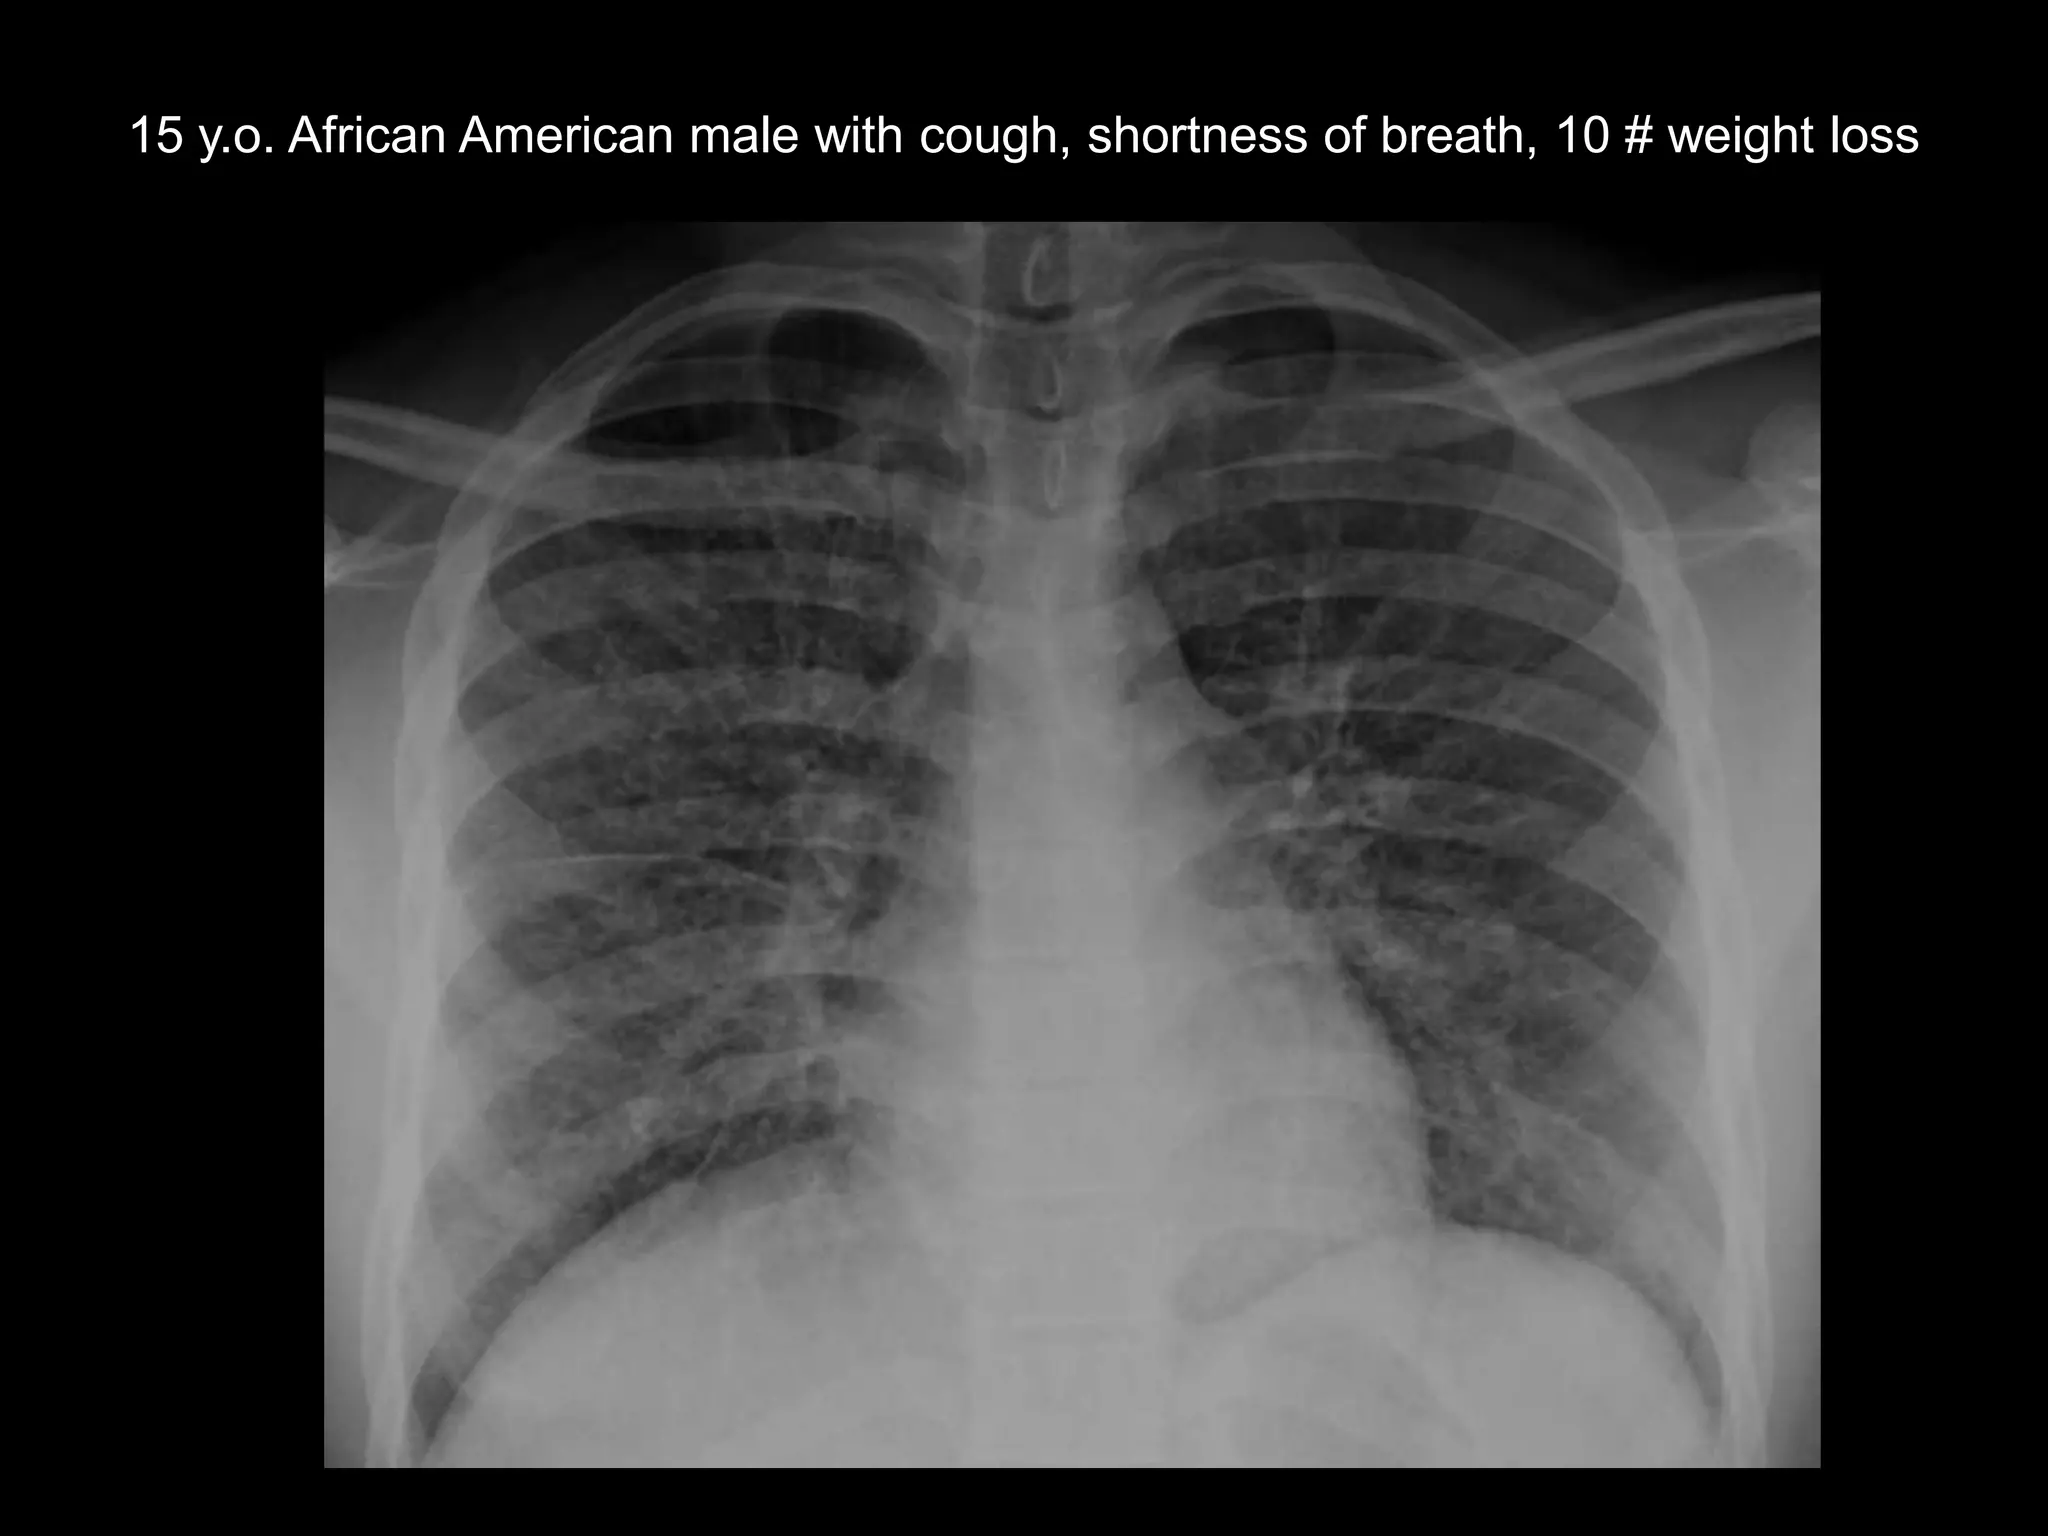

15 y.o. African American male with cough, shortness of breath, 10 # weight loss

Findings

• CXR – interstitial, septal

thickening

• Chest CT – septal

thickening, multiple small

nodules, ground glass opacities

• Abdominal CT –

infiltrative, indistinct left renal

mass

Pulmonary lymphangitic metastases

Metastatic renal medullary carcinoma

• Demographics:

– Seen almost exclusively in pts with sickle trait

– Age range = 11 – 39, Male: female=3:1

• Symptoms: pain, hematuria, wt loss

• Renal mass imaging features

– Infiltrative, associated necrosis, caliectasis

– More commonly right-sided

• Often widely metastatic at dx

– Pulm lymph spread is common